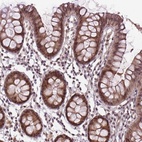

Immunohistochemical staining of human colon shows moderate nuclear positivity in glandular cells.